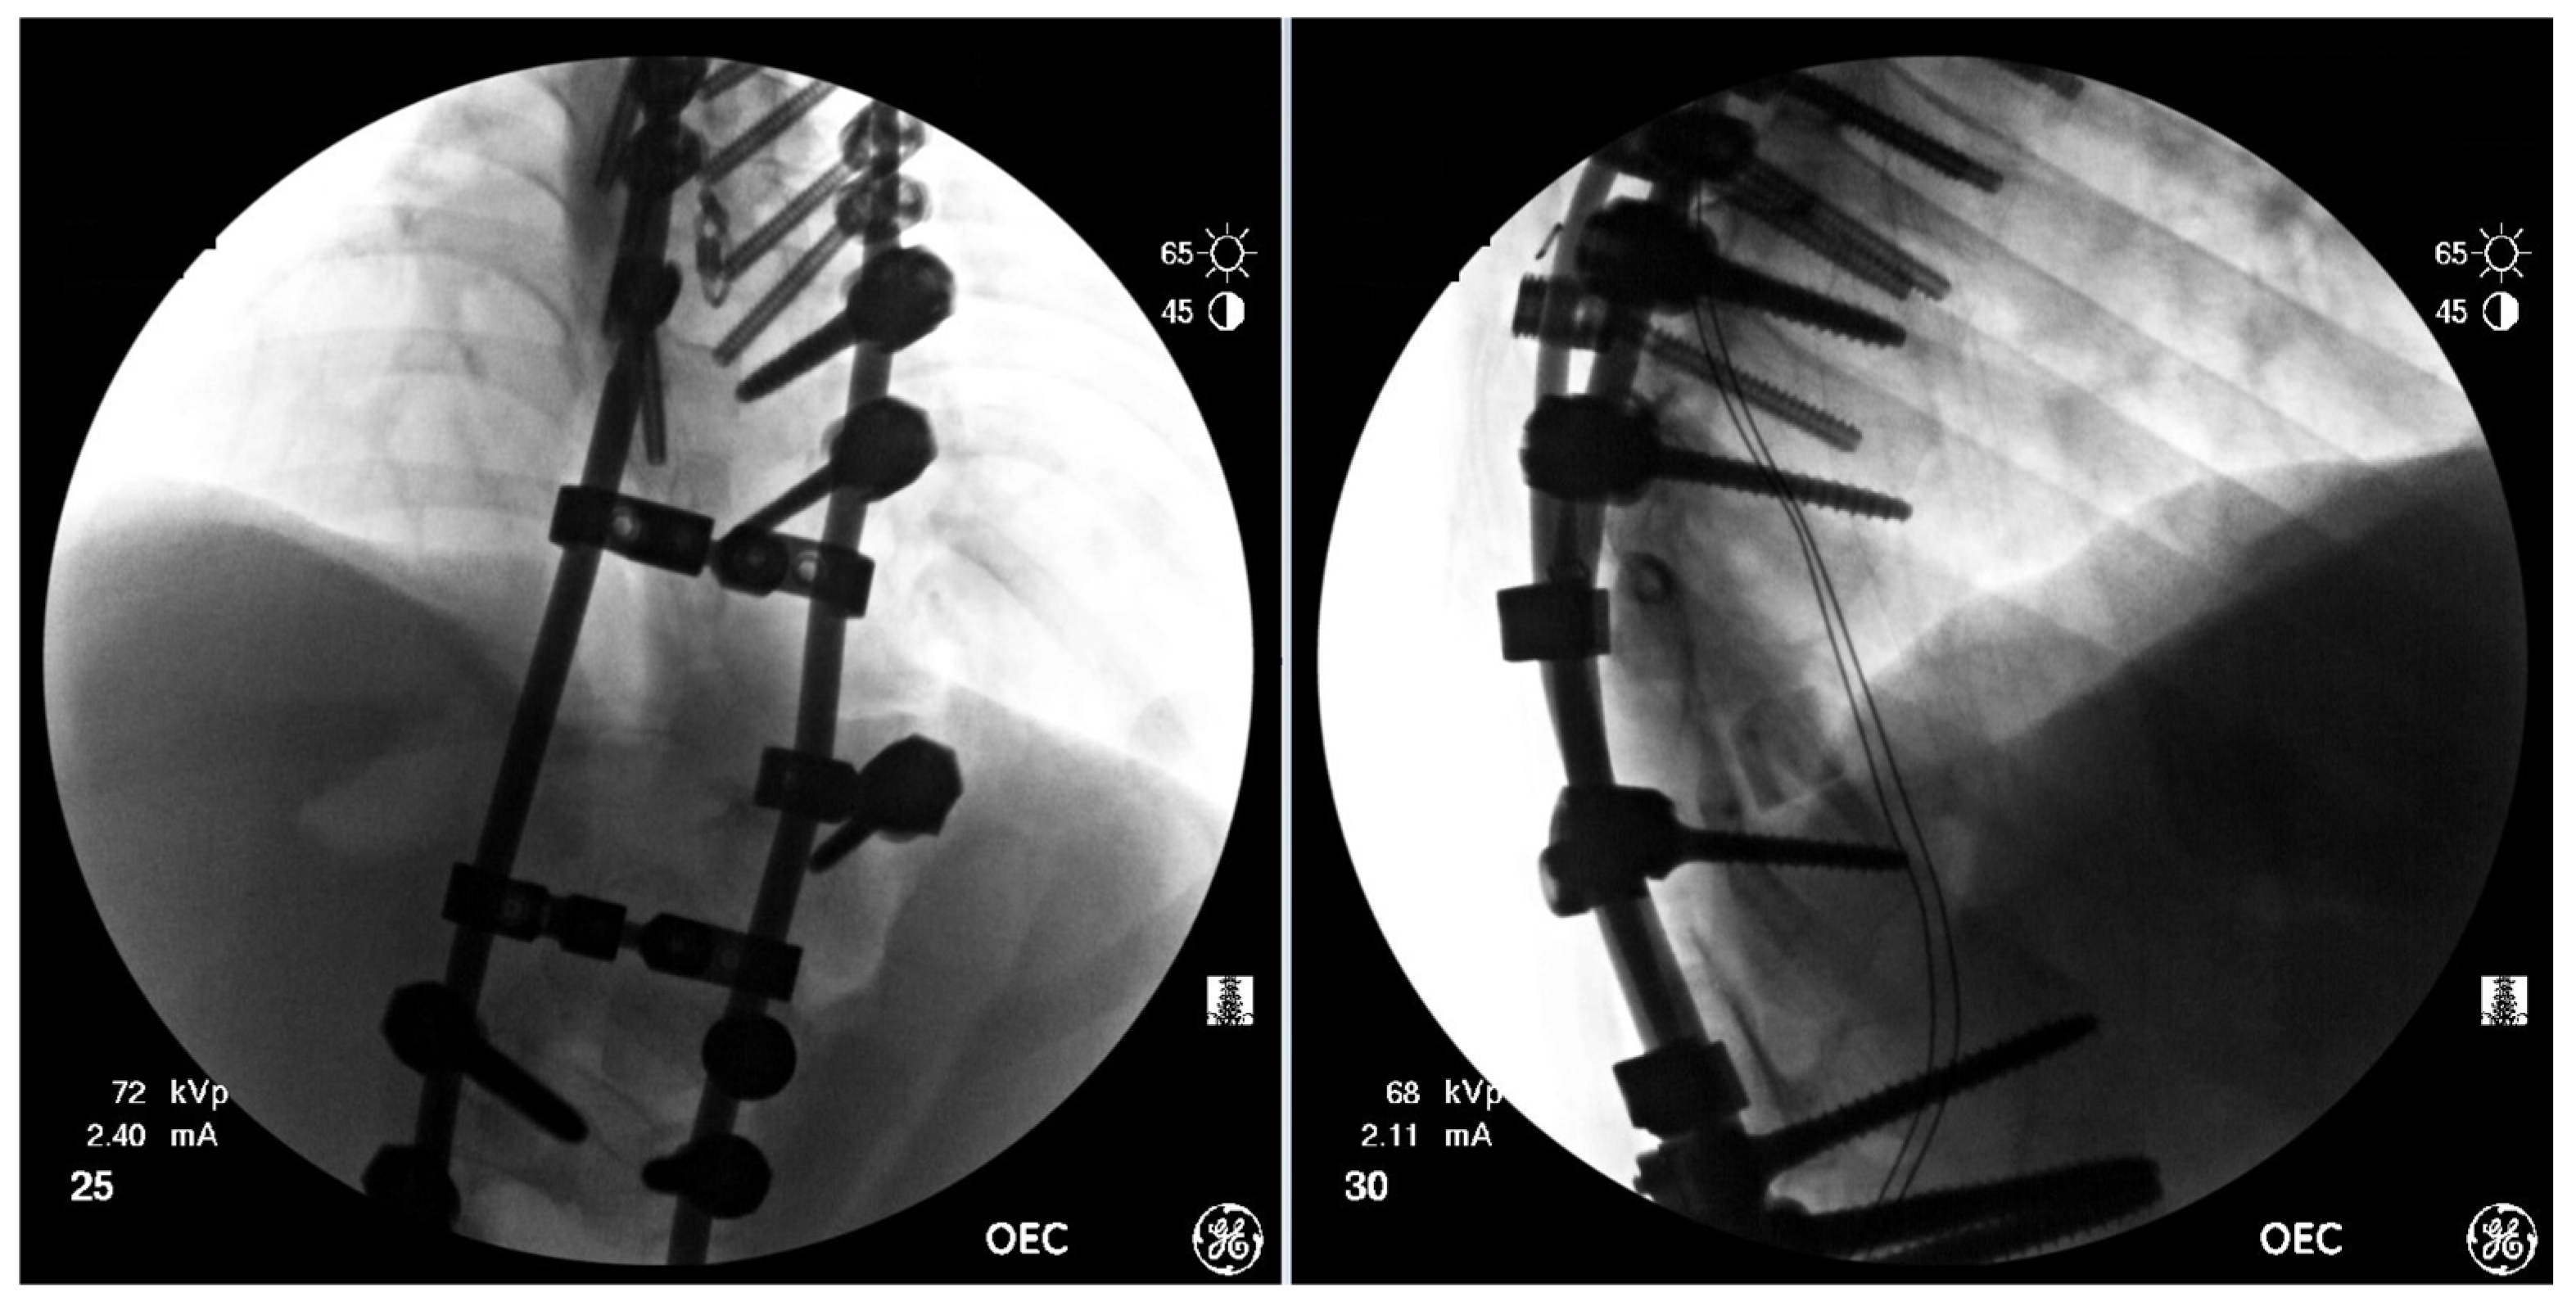

Figure 8.

AP & Lateral fluoroscopy images of the final instrumentation & deformity correction.

Strategic distraction, compression and de-rotation were used to achieve further correction–reduction of the kyphosis–slowly, using the rod exchange maneuver multiple times with temporary rods. Once substantial correction was achieved, these were exchanged with definitive rods placed from T5 to L4. After fine-tuning the correction, the MEPs did improve with tibialis anterior MEPs returning on both sides. Two cross links were placed over the vertebral body resection site. With the final correction achieved, further bone graft was applied across the posterolateral gutters, the facet joints and the corpectomy defect site, and the wound was closed (Figure 8).